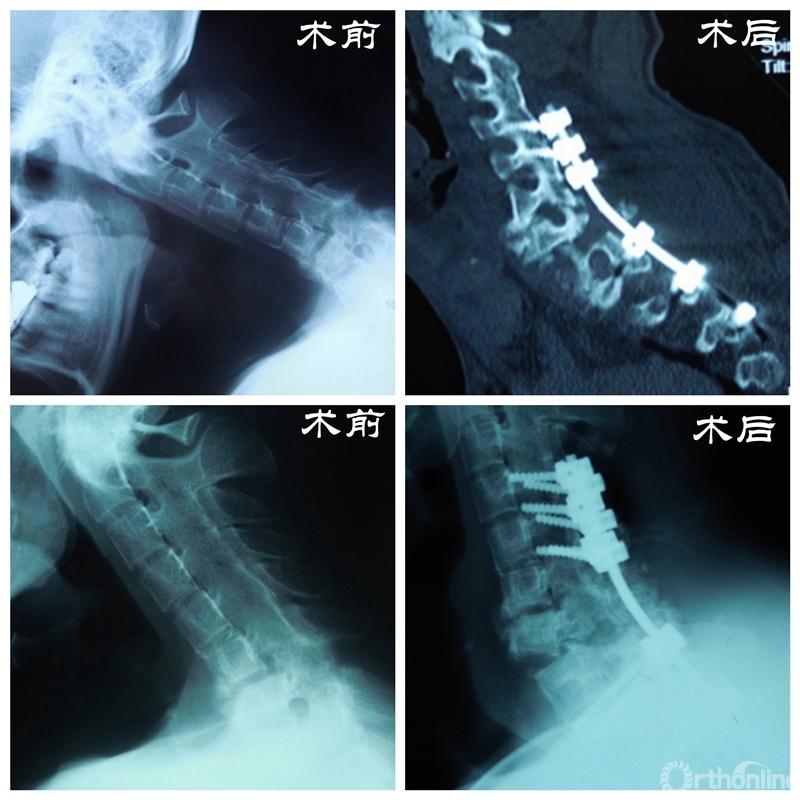

患者资料

门诊结束后,丁文元教授立刻带领团队成员开始查阅大量相关文献,为大帅的手术进行充足的准备和周密的计划。幸运的是手术很顺利,术后复查各项指标恢复良好,大帅的头也抬起了来了,脸上洋溢着久违的笑容,这给了医生和患者家庭极大的信心。

手术步骤

2015年的除夕夜,一通陌生的电话铃声掺杂着新年的热闹气氛响起。丁文元教授接起电话才得知是患者大帅,他激动的告诉丁文元教授:“我现在恢复的很好,并且已经结婚了!”。一番感谢过后便挂了电话,但丁文元教授却久久不能平静,这是他收到的最好的新年礼物。